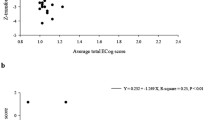

There were no significant associations between [18F]BCPP-EF DVRCS−1 and IQ as predicted by the national adult reading test, or between BCPP-EF DVRCS−1 sand Trail Making A scores in any brain region (n = 18, Pearson’s correlation, Z < 2.3, cluster threshold p > 0.05). There were also no significant associations between RAVLT total learning and delayed recall measures (n = 20, Pearson’s correlation, Z < 2.3, cluster threshold p > 0.05). There were significant associations between RAVLT recognition scores and [18F]BCPP-EF DVRCS−1 in regions spanning occipital, parietal and temporal areas, including the superior and middle temporal gyrus, postcentral gyrus and precuneus (n = 19, Pearson’s correlation, Z > 2.3, cluster threshold p < 0.05). Correlation coefficients for the significantly correlated clusters are shown in Fig. 2, an unthresholded correlation map is shown in supplementary Fig. 1 for reference.

Pearson’s correlation coefficients for clusters where [18F]BCPP-EF DVRCS−1 was significantly correlated with RAVLT recognition performance in cognitively healthy adults. (n = 19, Pearson’s correlation, Z > 2.3, cluster threshold p < 0.05). Axial slices in MNI152 are: -12 -2 8 18 28; 38 48 56 66 76, results are shown in neurological formal (L = L).